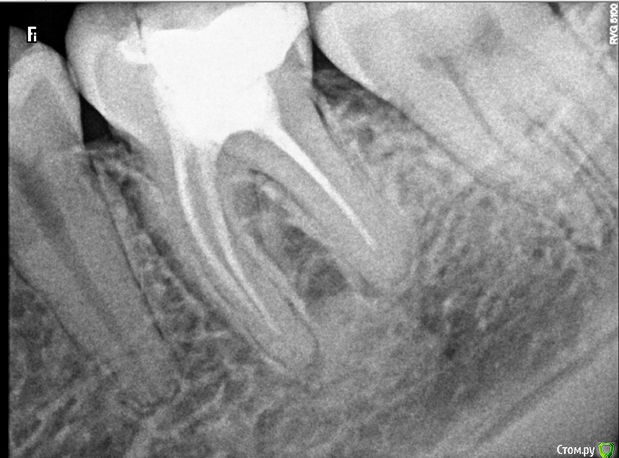

Свежий фрагмент ОПТГ

post-50922-0-16106800-1493654508_thumb.jpg

Нижний зуб 6-ка, депульпирован около 11 лет назад. Два года назад обновляли пломбу на нем.

Последние 2 месяца стала чувствовать зуб, неприятные ощущения в нем появились и ощущение как бы давления.

Требуется перелечивать каналы? Похоже ли то, что я вижу у корней на кисту?